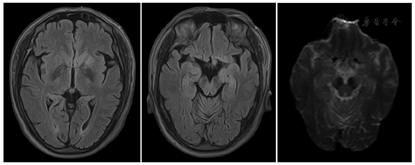

MRI:左侧基底节区及左侧海马在T2 Flair及DWI上见片状稍高信号,缺血性改变(图1)?18F-FDG PET/CT(发病20 d):双侧尾状核体部、左侧尾状核头、双侧壳核、左侧颞叶内侧(包括左侧海马-杏仁核复合体)、左侧额叶内侧及左侧岛叶代谢增高,全身未见明确恶性肿瘤征象(图2)。

据报道,超过95%的抗IgLON5抗体相关脑病患者的MRI表现不明显或非特异性,多为轻度至中度脑干、双侧海马和小脑萎缩,T2 Flair信号增高[1]。影像学上抗LGI1抗体脑炎主要表现在边缘系统,包括海马、杏仁核、颞叶、岛叶及扣带回皮质结构,基底节受累为不典型表现,MRI上为上述部位的T2WI及T2 Flair序列的高信号[7]。本例头颅MRI显像示左侧基底节区及左侧海马的T2 Flair及DWI信号略增高。国内一项研究从9个医疗中心招募了13例抗IgLON5抗体阳性的患者,其中4例接受18F-FDG PET检查,1例患者表现出双侧脑白质代谢下降,2例患者表现出颞叶代谢下降,1例患者表现出双侧额叶和双侧基底神经节的FDG代谢略有增加[3]。苏柳迪等[7]报道的5例LGI1抗体脑炎患者的18F-FDG PET/CT发现,3例为尾状核、海马及颞叶的代谢增高,1例颞叶的代谢减低,1例代谢未见异常。本例因CEA及非小细胞肺癌抗原稍升高,临床为排除肿瘤,行全身的PET/CT。18F-FDG PET/CT显示双侧尾状核体部、左侧尾状核头、双侧壳核、左侧颞叶内侧(包括左侧海马-杏仁核复合体)、左侧额叶内侧及左侧岛叶代谢增高,全身未见明确恶性肿瘤征象。18F-FDG PET/CT较MRI发现病变的范围更大且更明显,提示18F-FDG PET/CT在脑炎的敏感性更高。本例患者的MRI及18F-FDG PET/CT的表现均以基底节及边缘叶系统受累为主,其中边缘叶受累与典型的抗LGll抗体脑炎影像学改变相符。